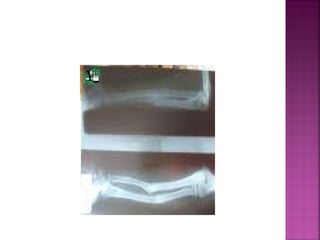

En los niños, debido a la gran

elasticidad de sus huesos,

se producen dos tipos

especiales de fractura:

 Incurvación diafisaria: no

se evidencia ninguna

fractura lineal, ya que lo

que se ha producido es un

aplastamiento de las

pequeñas trabéculas óseas

que conforman el hueso,

dando como resultado una

incurvación de la diafisis

del mismo.

EN TALLO VERDE

(incompleta)

•El hueso está

incurvado y en su

parte convexa se

observa una línea

de fractura que no

llega a afectar todo

el espesor del

hueso.